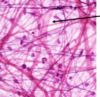

סיבים רטיקולריים - הרכב ומאפיינים

נוצרים בעיקר מקולגן מסוג 3 יחד עם פרוטאוגליקנים וגליקופרוטאינים.

סיבי קולגן דקים במיוחד שיוצרים רשת מסביב לאיברים שונים כמו כלי דם, עצבים, שרירים, בלוטות לימפה וטחול.

הרשת הרטיקולרית היא גמישה.